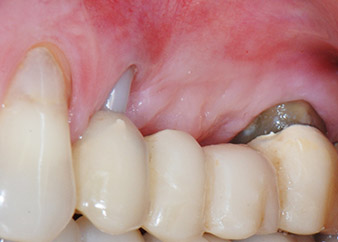

Un mois plus tard, le jour de l'intervention, la douleur et l'inflammation sur la dent 24 étaient minimes mais une mobilité de classe 2 de Miller était toujours observable. Après ouverture des lambeaux et nettoyage des tissus périapicaux et périradiculaires infectés, l'étendue du défaut osseux est devenue parfaitement visible (Figures 2 et 3).

À la racine de la dent, il manquait la totalité de l'os vestibulaire et distal. L'attache était essentiellement limitée à la racine palatine, venant ainsi confirmer le pronostic défavorable initial. La dent 27 présentait également une attache horizontale réduite et une raréfaction apicale minime (cf. Fig. 1), sans symptômes cliniques.

perte totale d'os et d'attache

Fig. 2 et 3 : Après élévation des lambeaux, un mois après le retraitement endodontique et le démarrage du traitement parodontal global, la racine de la dent 24 présentait une perte totale d'os et d'attache.